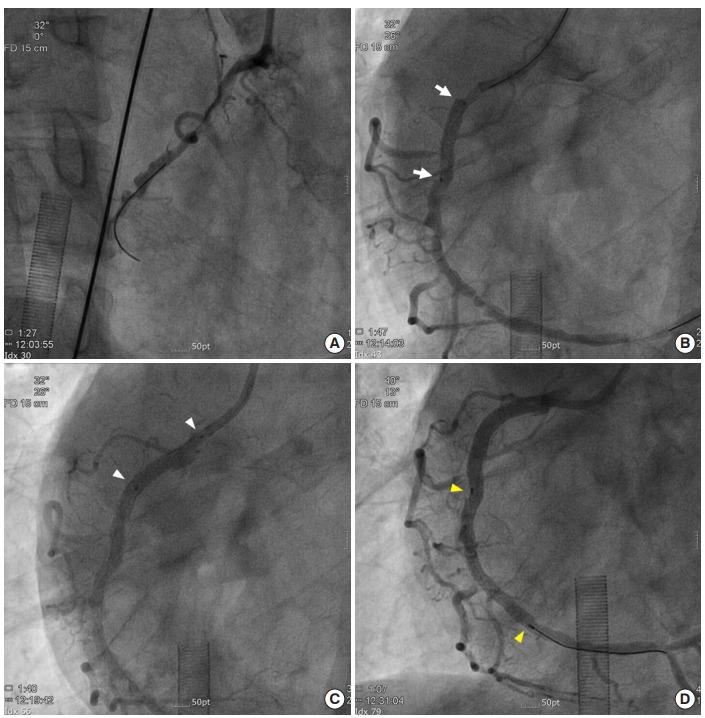

The presentation of coronary artery disease in a patient with Eisenmenger syndrome (ES) is relatively rare. Cardiogenic shock due to coronary artery dissection during percutaneous coronary intervention (PCI) can be more critical in these patients. Here, we report a case of successful PCI under mechanical circulation support in a patient with ES who experienced potentially fatal right coronary artery dissection. This case emphasizes that use of extracorporeal membrane oxygenation (ECMO) can lead to successful management of critical complication during PCI, and that the immediate decision to apply of ECMO is important in ES patients who face impending cardiogenic shock with acute heart failure.

艾森曼格综合征(ES)患者出现冠状动脉疾病的情况相对少见。在这些患者中,经皮冠状动脉介入治疗(PCI)期间因冠状动脉夹层导致的心源性休克可能更为危急。在此,我们报告一例ES患者在机械循环支持下成功进行PCI的病例,该患者发生了可能致命的右冠状动脉夹层。本病例强调,体外膜肺氧合(ECMO)的使用可成功处理PCI期间的严重并发症,对于面临急性心力衰竭即将发生心源性休克的ES患者,立即决定应用ECMO至关重要。